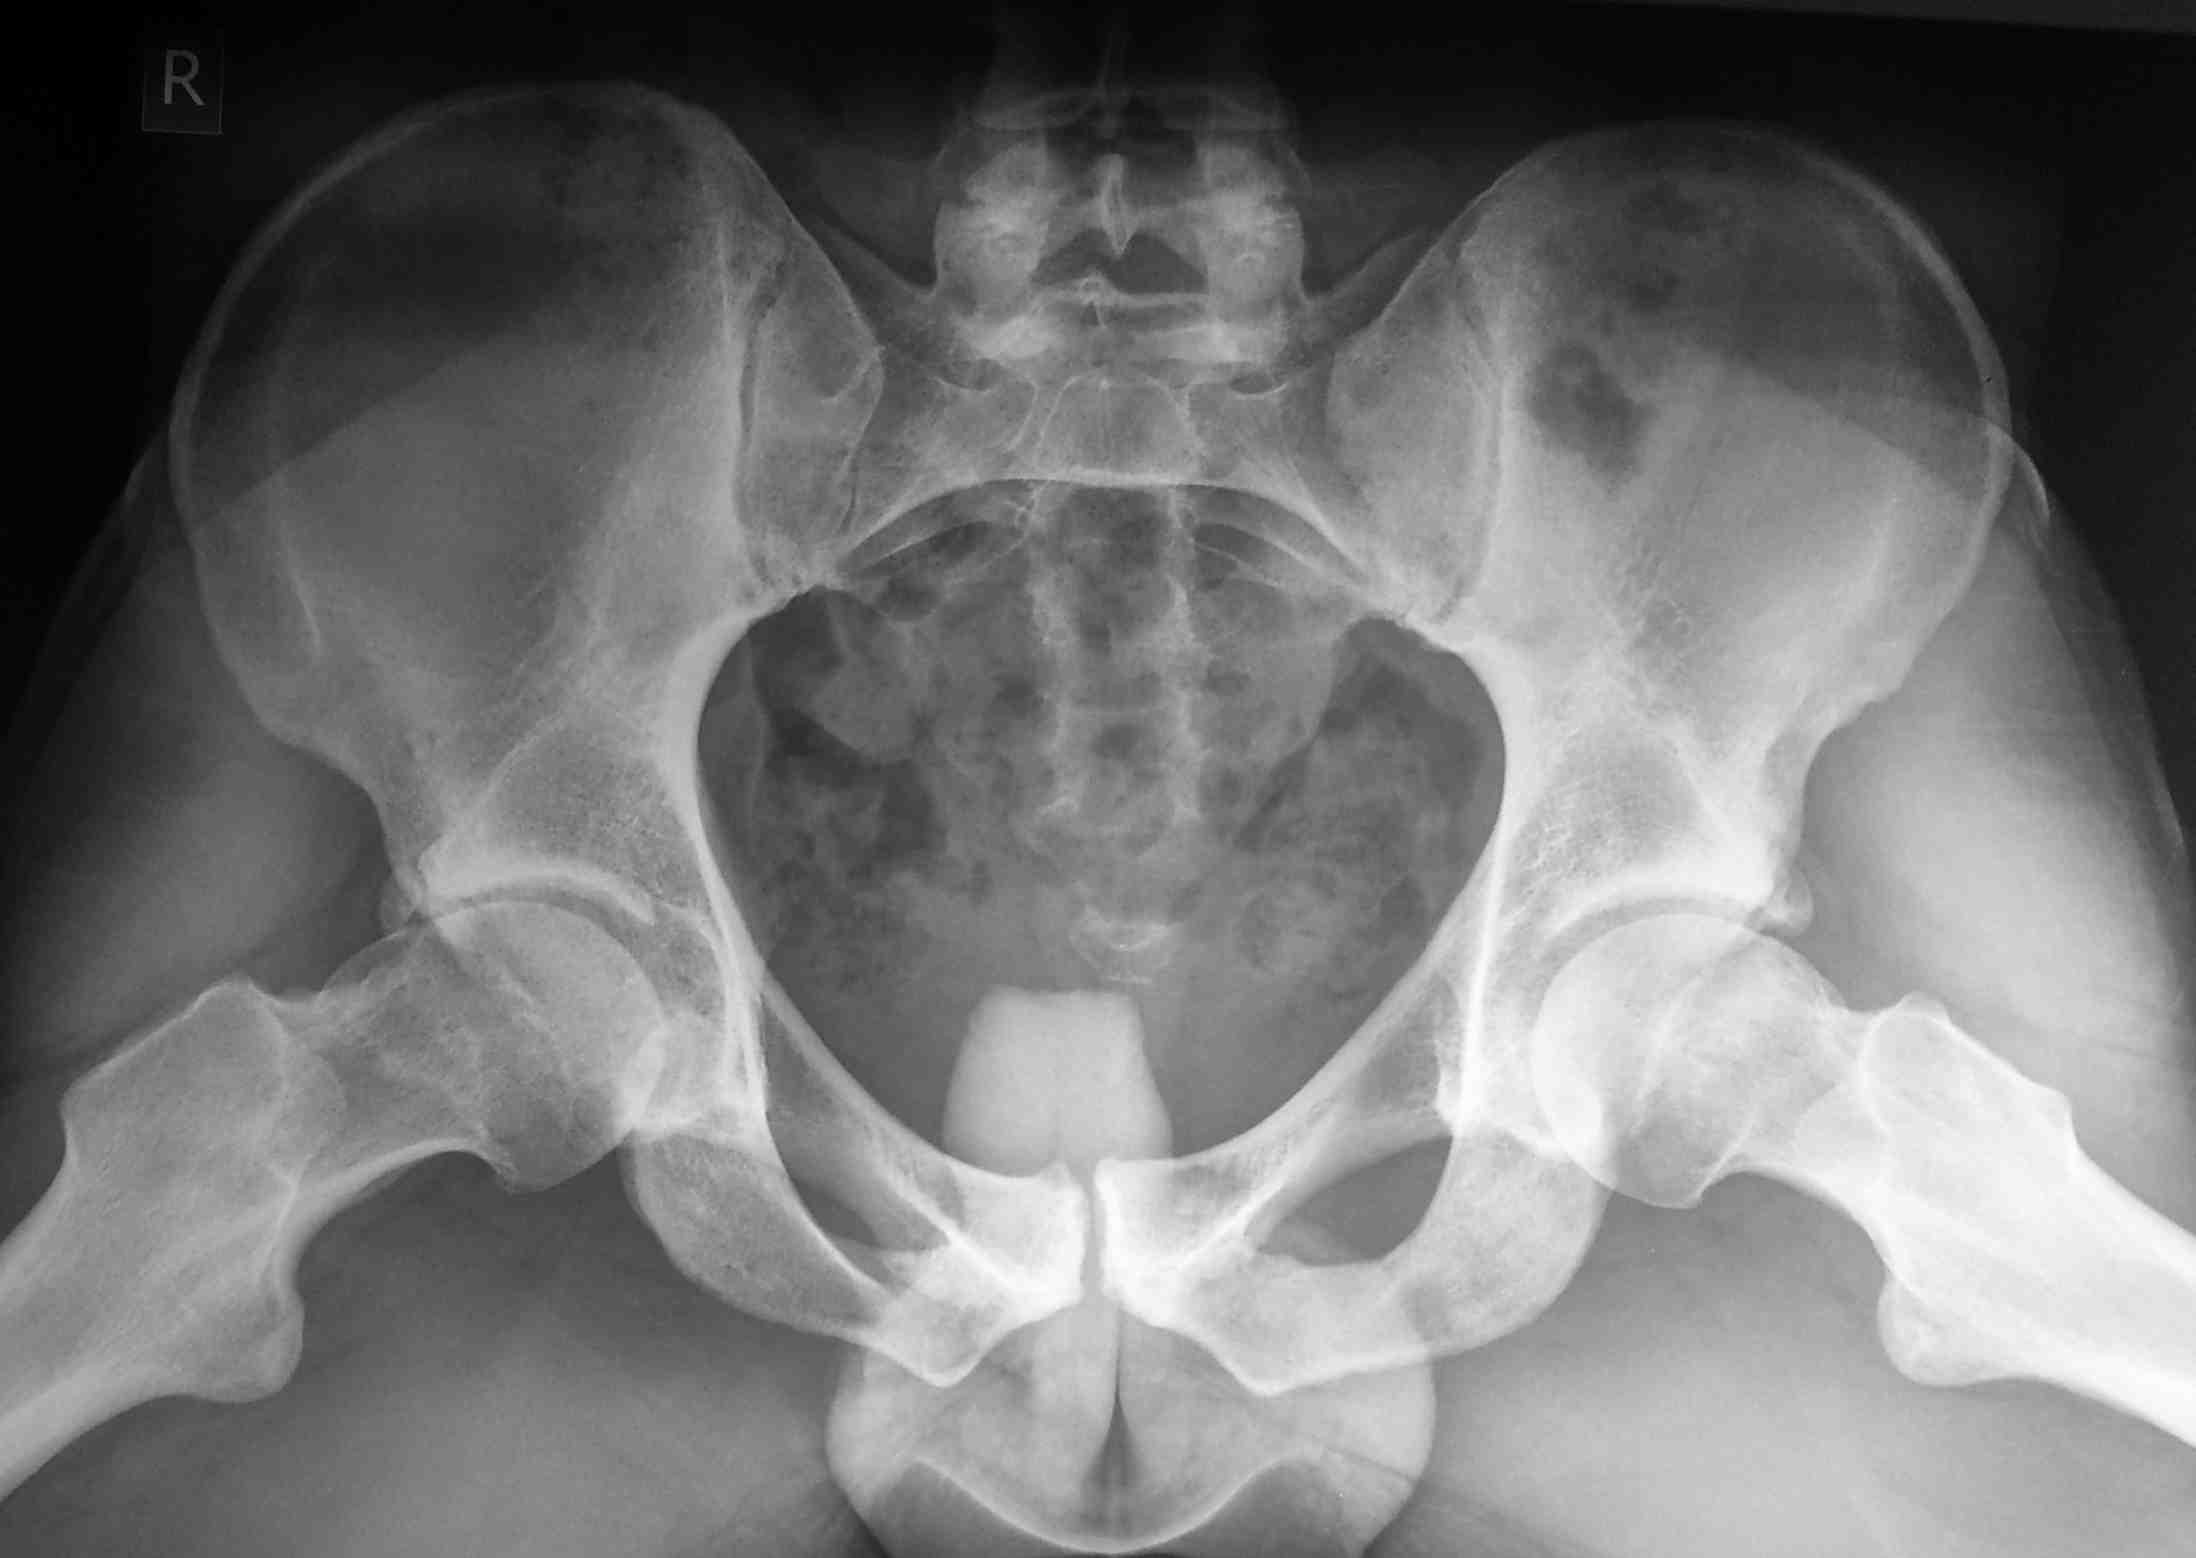

3.3-ий значит : Бернская (город) хирургическая дислокация бедра по Ганцу (автор).Синонимы:Бернский доступ, доступ со скольжением большого вертела (sliding trochanteric osteotomy), доступ с переворачиванием большого вертела (trochanter flip osteotomy), безопасная хирургическая дислокация бедра (safe surgical hip dislocation) двубрюшный доступ ("le muscle digastrique").

Насколько он безопасный демонстрирую интраоперационное фото при выполнении шеечной остеотомии при юношеском эпифизеолизе.

С ув. Филипчук

P.S. Длительность наблюдения 7 лет, признаков аваскулярного некроза не наблюдали. Кстати. это мой первый доступ по Ганцу, так что learning curve ( кривая обучения) не слишком крутая.